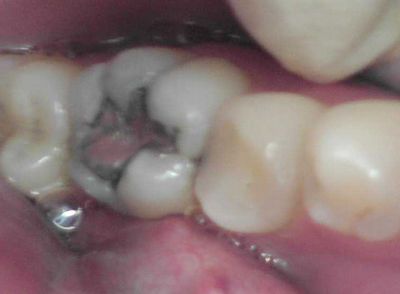

神経がこんな感じに腐ってたらもう、取るしか方法ないですわな。

左下5番、充填してあるようなのだが、元々虫歯が深かったようだ。

自発痛(-)、冷水痛(+)、咬合痛(+-)。

中の齲蝕を少しずつ取って行くと、露髄した。

周囲に軟化象牙質もなく出血もなかったので、

MTAセメントで歯髄の保存を試みました。

CR充填して終了。